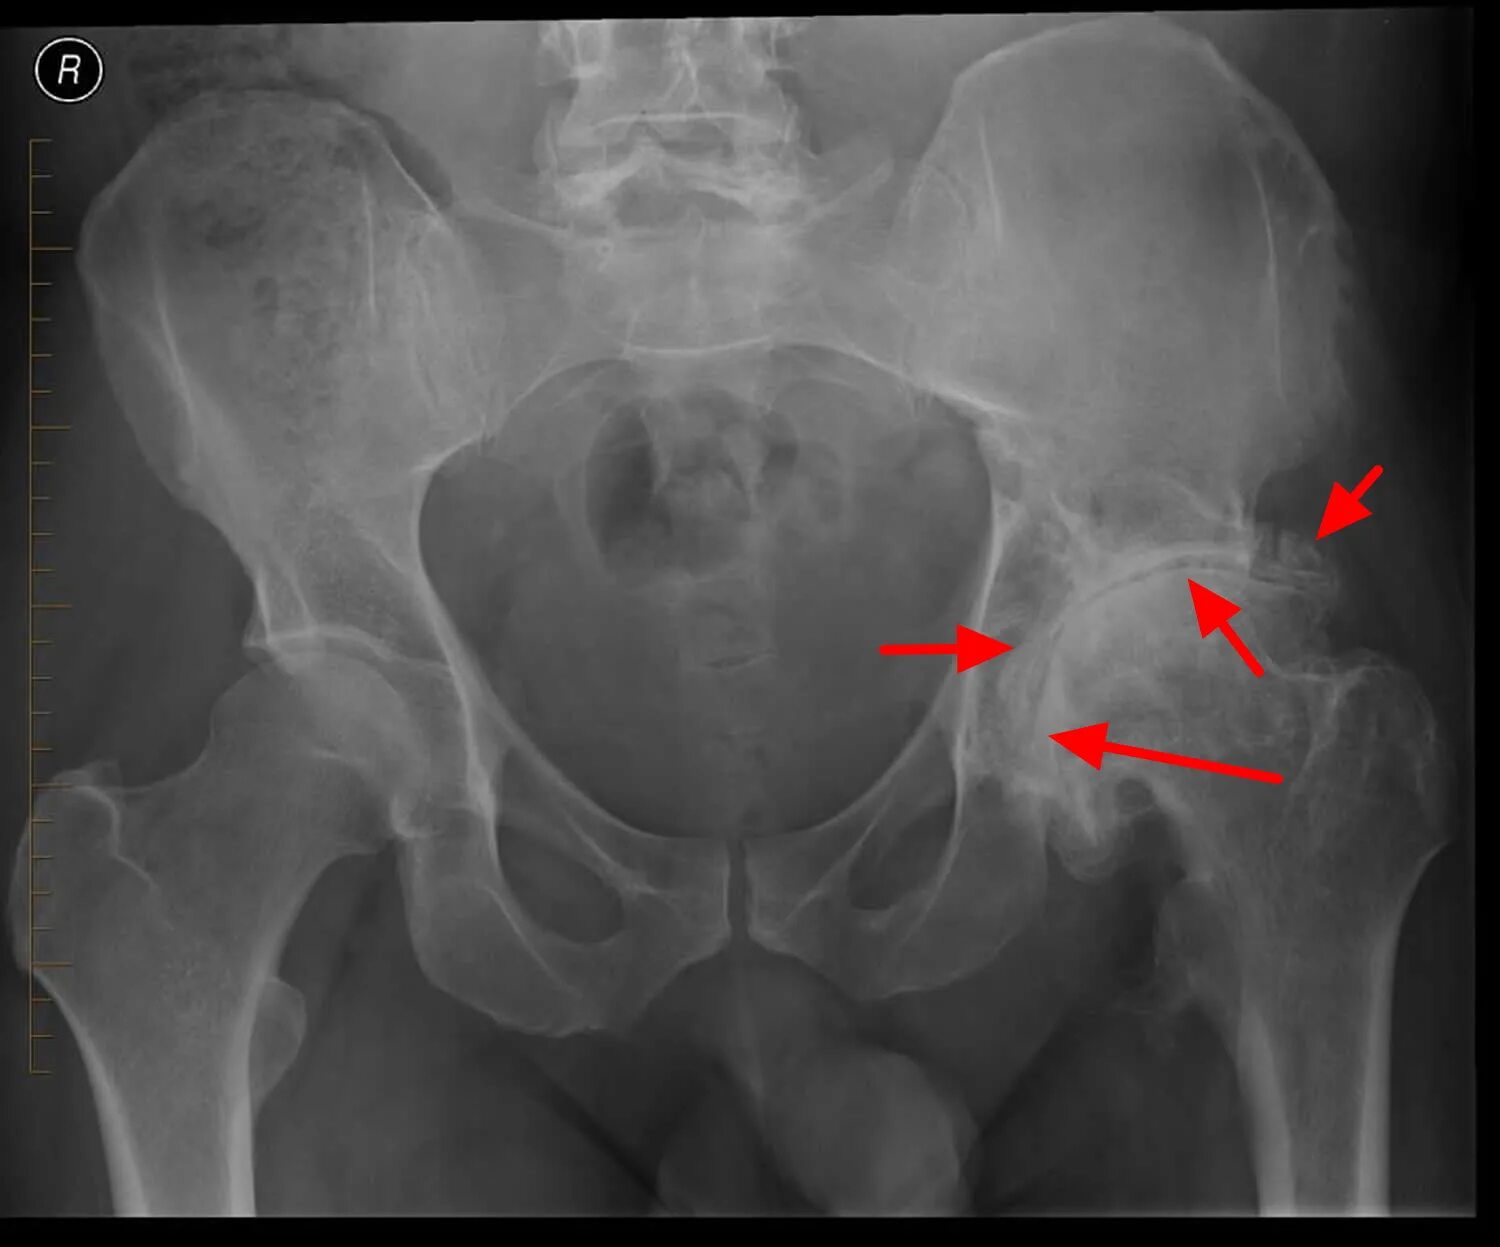

Остеоартроз тазобедренных суставов 1 2